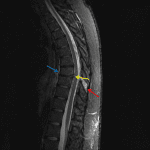

- Trace retrolisthesis and focal kyphosis at T8-T9 with narrowing of the anterior aspect of the disc space

- Ill-defined area of STIR signal hyperintensity in the left aspect of the T9 superior endplate

- T2/STIR signal hyperintensity in the ligamentum flavum, bilateral facet joints, and interspinous and supraspinous ligaments at T8-T9

- Inferiorly dissecting central disc extrusion at T8-T9, which effaces the ventral CSF and contacts the ventral cord, resulting in mild spinal canal stenosis

- Resultant uplifting and possible focal disruption of the posterior longitudinal ligament at the level of T8-T9

- Possible focal disruption of the anterior longitudinal ligament at the level of the T8 inferior endplate

- No cord signal abnormality

- Small posterior disc herniation at T4-T5 without significant spinal canal stenosis

Flexion-distraction injury at T8-T9 with likely disruption of the anterior longitudinal ligament, posterior longitudinal ligament, and ligamentum flavum at this level, bilateral facet capsular injury, and interspinous and supraspinous ligament injury. Nondepressed impaction fracture in the left aspect of the T9 superior endplate.

Traumatic disc extrusion at T8-T9, which contacts the ventral cord and results in mild spinal canal stenosis. No cord signal abnormality. No significant epidural collection.